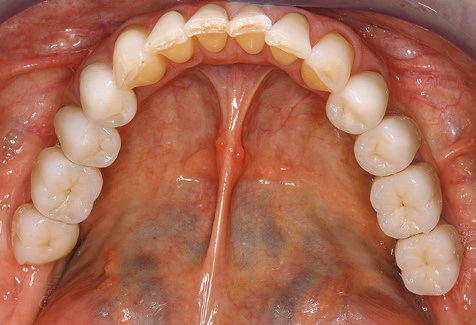

A 52-year-old patient presented in our clinic for the first time in 2004 following tooth loss in the third quadrant, expressing a desire for a new prosthetic restoration. Periodontal and radiological diagnostics revealed the need for extensive periodontological treatment. In addition, teeth 48, 28 and 27 were attributed a very poor prognosis and were subsequently extracted (Fig. 1). Following the successfully completed, systematic periodontological treatment, a fixed dental implant was inserted with the introduction of five implants in tooth regions 35, 36, 37, 46 and 47. Prosthetic treatment of the natural teeth was effected with veneered zirconium dioxide ceramic crowns; the implants were composed of two-piece, individual zirconium dioxide abutments and similarly veneered crowns made of a zirconium dioxide ceramic (Cercon base colored, Dentsply Sirona Lab). Definitive insertion of the prosthetic restoration occurred in 2005.

Due to the presence of periodontal disease, SPT was performed every three months in the first years following the insertion. The patient demonstrated a high degree of motivation and good compliance. The pocket depths recorded annually revealed a stable periodontal situation with a BOP index of below five per cent. On the basis of the stable periodontal situation and good cooperation on the patient’s part, the recall interval was extended to every six months as of the sixth year of the prosthetic function phase. Following the change in the recall interval, the respective annual documentation of the periodontal status continued to reveal a stable periodontal situation with no increase in the pocket depths and a BOP index below five per cent (Fig. 2a and b).

The ten-year check-up revealed no indications of advancing clinical attachment loss or peri-implant bone substance loss (Fig. 3).

The patient continues to visit the clinic every six months for SIT. In the following, the patient is taken as an example for demonstrating the individual working steps in a structured SPT session as it has been performed with barely any modifications over the last 12 years. Of course, some new materials and devices have been integrated into the concept over the years. This clinical case report presents the current material and device concept.

Standardised and regular risk-adapted care in the scope of SPT is the key to treatment success for the clinical long-term success in periodontically compromised patients. This is particularly true for patients fitted with implants following successfully completed periodontal treatment (Fig. 11a and b).